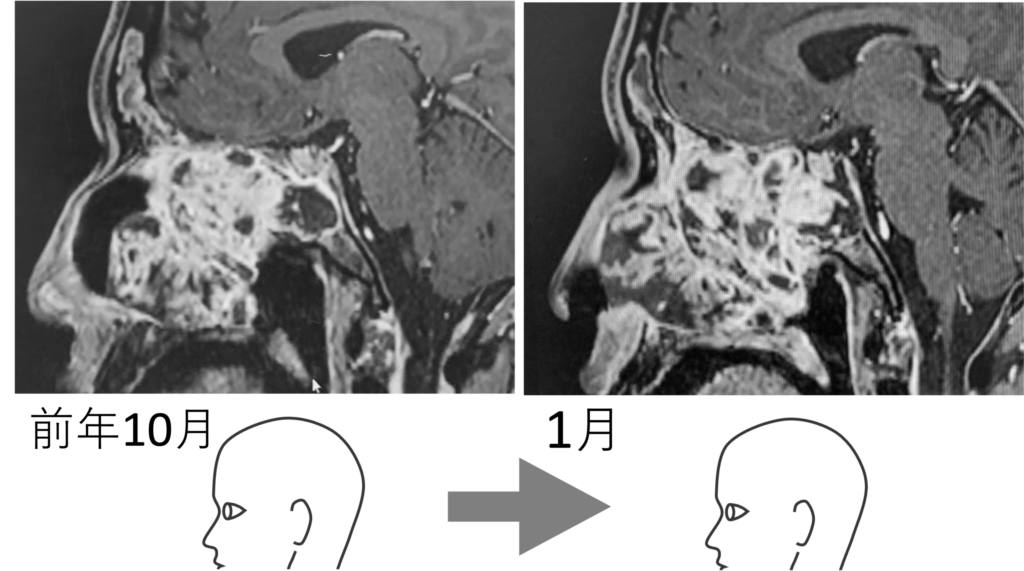

前年10月の画像を見ると、ガンの向かって左 (鼻のあたり) に空洞があることが分かる。まだガンが大きくなるスペースは残されていた。ところが1月の画像をみるとその空洞はなくなっている。もうガンが大きくなるスペースがなくなり、すし詰め状態となっている。こうなると、やがて脳幹 (画像の青色でなぞった部分) をガンが襲うことになる。これは死を意味する。後述するが、ドクターが予測した その時“” は、3月中であった。10月から1月にかけての巨大化の速度から、この調子で行くと3月に脳幹に達すると推測したのだ。